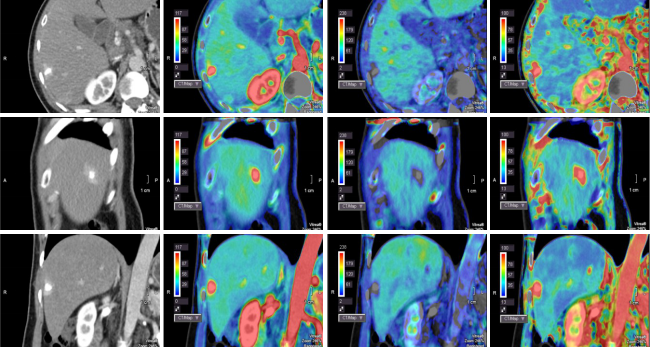

8、腫瘤應(yīng)用(全器官灌注)

病例一 34歲, 男, 右肝血管瘤。

灌注檢查可見(jiàn)肝臟內(nèi)一類圓形病灶,AF為血流高灌注,PF為血流低灌注。

可以自動(dòng)一鍵提取肝動(dòng)脈、 門靜脈以及腫瘤, 并且進(jìn)行融合, 觀察腫瘤與動(dòng)脈及門脈血管的關(guān)系。

640層寬體探測(cè)器CT對(duì)于肝臟全器官灌注掃描,不但能夠精確顯示動(dòng)脈期、門脈期、靜脈期的3D解剖結(jié)構(gòu),而且可以同時(shí)探查腫瘤的供血?jiǎng)用}、流出靜脈,分析肝實(shí)質(zhì)的血供和灌注情況。所有這些檢查都以極低的劑量在一次檢查中完成,對(duì)肝腫瘤的診斷與治療及效果評(píng)估具有重大意義。除此之外,特有的肝血管融合技術(shù),可用于肝臟手術(shù)模擬以及肝臟腫瘤的分割和量化。